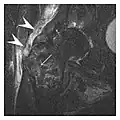

Proximal femoral fractures usually occur in osteoporotic patients, and their signs include subtle neck angulation, trabecular angulation, and subcapital impaction line. A frog-leg lateral view may be helpful if the greater trochanter is short enough. However, positioning can be difficult because of hip pain. In patients with strong suspicion of proximal femoral fracture and negative radiographs, MRI limited to coronal T1 W images and scintigraphy can be highly valuable (Figures 13 and 14). Such an option, with limited examination time, is cost-effective and allows reliable exclusion or confirmation of the diagnosis, preventing an unnecessary stay at the hospital or delayed treatment. Moreover, MRI helps to detect soft tissue abnormalities which are more frequently seen in femoral, acetabular, and pubic injuries than sacral lesions. Concomitant fractures are also frequently seen in typical pelvic sites.[1]

Figure 13: Partial osseous avulsion of the gluteal muscles at the greater trochanter in a 59-year-old man who presented with the right hip pain without a history of trauma. Lauenstein view and anteroposterior and radiographs (not shown) did not show an obvious fracture line or disruption of bony contours in the acetabulum or the right femoral neck. (a) Coronal T1-weighted MRI displays an incomplete fracture line extending partially from the greater trochanter (arrow). (b) Coronal short tau inversion recovery MRI shows heterogeneous hyperintensity in the same region (arrow) as well as hyperintensity within the gluteus medius and minimus muscles (arrowheads) consistent with tissue edema and hematoma.[1]